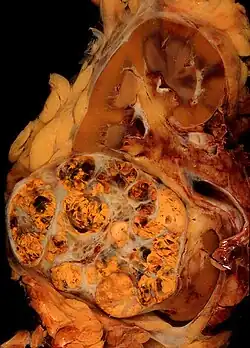

Clear-cell renal-cell carcinoma. Macroscopy -